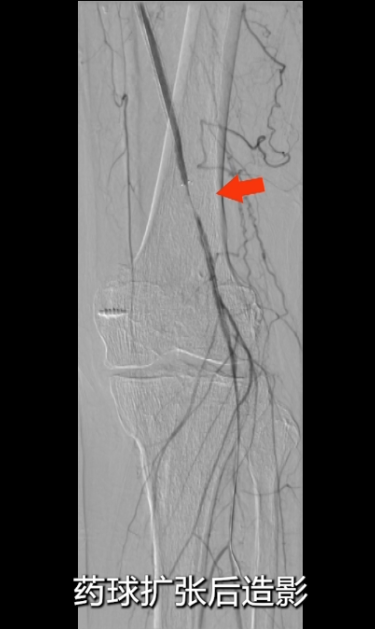

药物球囊扩张后造影显示:支架远端(临近P2段)存在局部狭窄,使用5×150mmIris球囊对病变段再次预扩;

扩张后出现小夹层,血流速度仍较慢,采用4×80mmIris球囊对病变段再次预扩